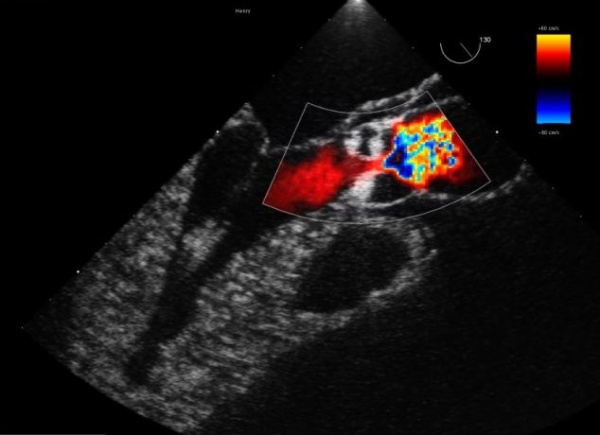

Эхокардиография при коарктации аорты. При проведении данного исследования необходимо ответить на следующие вопросы: 1. Имеется локальная коаркта-ция или тубулярное сужение перешейка аорты? 2. Какова степень выраженности коарктации? 3. Каково направление потока крови через ОАП? 4. От какой области аорты отходят подключичные артерии? 5. Есть ли дополнительные ВПС, в том числе гипоплазия дуги аорты? 6. Насколько нарушена насосная функция сердца?

Для сканирования аорты наиболее часто используется супрастернальная позиция. В норме при двухмерном изображении аорта выглядит на экране эхокардиографа как дугообразное образование без каких-либо сужений, с симметричной пульсацией по всей длине. На участке коарктации аорты визуализируется сужение просвета с активной пульсацией выше этого места.

Косвенными признаками, подтверждающими коарктацию, могут быть постстенотическое расширение аорты, гипертрофия и дилатация желудочков. При использовании допплер-методики регистрируются турбулентный кровоток в месте сужения аорты и сниженный кровоток в брюшном отделе аорты.

Особенно важно выявление гипоплазии дуги аорты, что влияет на объем хирургического вмешательства. Опорным моментом является сравнение диаметров дуги аорты и нисходящей аорты. Гипоплазию дуги можно заподозрить при отношении этих диаметров менее 0,7. Другим вариантом является сравнение диаметра дуги аорты с диаметром восходящей аорты (до отхождения безымянного ствола). В норме их отношение должно быть более 0,5.

Видео ЭхоКГ при коарктации аорты у плода